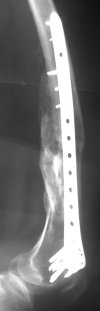

Synthes 4.5 mm LCP (Locking Condylar Plate) is slightly different, more anatomical shape and larger (wider) than original LISS. I personally use it when I have more difficult, Type C fractures where larger incision is necessary in order to reconstruct the joint.

For cases with less comminution and those that require longer plates (more involvement of distal third of femur), I rather go with LISS because is

possible to put the screws truly percutaneously (stab incisions, outside guide). Both systems are available and in use... :) .